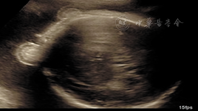

病例1,孕妇26岁,孕1产0,孕32周,平素月经规律,否认家族性遗传病史。孕期曾在外院行产前超声检查未见异常。因阴道流液1 d余,入我院行超声检查,胎儿生长参数与孕周相符。胎儿头皮水肿增厚约0.69 cm,颅内结构、心肺未见明显异常,胎儿胃、膀胱、双肾、脊柱可显示,羊水最大平段12.5 cm,羊水指数43.1 cm。胎儿两侧眼眶上方分别可见1.7 cm×0.9 cm、1.8 cm×1.1 cm的混合性回声肿块,肿块突出于体表(图1)。双眼及晶状体回声可见,下颌短小且内收,嘴唇呈微张状。动态观察,嘴唇未见闭合,舌头位于上下唇之间,双手呈握拳状,双足短小且姿势异常,足底皮肤厚约1.0 cm。羊膜腔内可见多条带状回声(图2)。超声提示:①单活胎,头位﹔②羊水过多﹔③胎儿头皮水肿,颜面异常,双侧眼眶上方软组织肿块﹔④胎儿双手及双足短小、姿势异常﹔⑤羊膜腔内多条带状回声。引产一女婴,大体标本见婴儿全身被一黄色角质样物质包裹,呈皲裂状,以头、面、颈、躯干、外阴部最明显;双唇增厚水肿外翻,牙槽外露;无鼻骨鼻翼,仅见两个鼻孔;眼睑外翻,双眼外上侧见两团红色肉样赘生物;小耳,仅有耳廓及耳孔,无耳道;小下颌;四肢呈弯曲状态,手足发育不全,脚掌呈"蹼形",指趾粗短,其关节肿大呈"兽爪样",外阴发育明显小于正常婴儿,肛门仅见裂隙。取小块黄色角质样物送病理检查提示角质层过度增厚,角化过度。根据临床表现及病理特征诊断:胎儿鱼鳞病。

此病胎儿全身皮肤增厚、皲裂,超声图像上显示胎儿皮肤呈"龟壳"样或"地图"样改变,尤以面部及头颅部皮肤显著。病例1超声显示羊膜腔内多条带状回声,为患儿皲裂的皮肤漂浮于羊水中。病例2属于轻型,故超声仅显示皮肤增厚。

胎儿因盔甲样皮肤常继发眼–耳–口的挛缩异常,声像图上常能显示双侧眼睑外翻、双耳发育不良、鼻骨发育不良等颌面部畸形,同时胎儿的嘴因挛缩牵拉而长大,持续张开不能闭合,因而胎儿双唇肥厚水肿外翻成为胎儿鱼鳞病的重要表现之一,声像图上胎儿双唇往往呈"鱼嘴"样改变,这一特异性表现有助于此病与其他颜面部畸形相鉴别。本组病例均可见双唇呈"鱼嘴"样改变及四肢的挛缩样改变,产后还可见眼部及耳朵的异常。